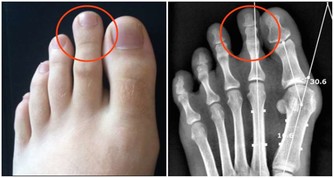

前列腺炎的典型症狀:

1.排尿不適:尿頻、尿急、夜尿多、尿道灼熱感。

2.射精不適:血精、射精痛。

3.局部疼痛:如肛周、下腹部甚至睾丸脹痛。前列腺炎的預防措施很簡單,從病因出發,即可有效預防。